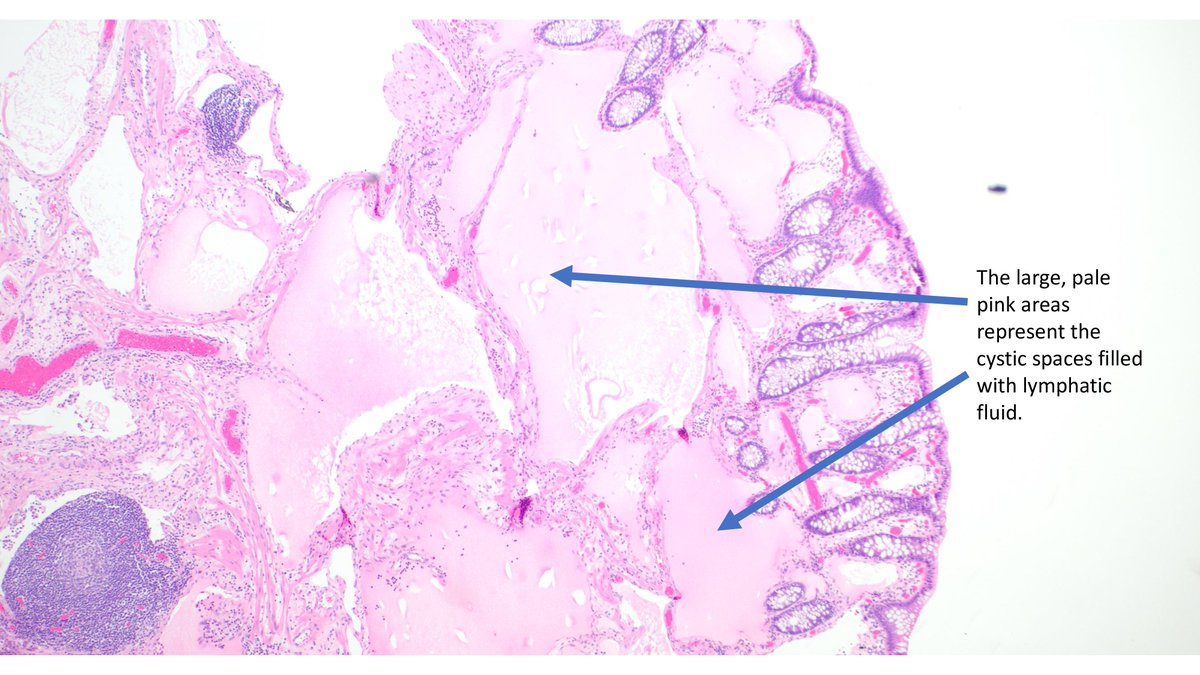

🔬 Colonic Lymphangioma Overview: •Primary (Congenital): Arises from malformation of lymphatic vessels. •Secondary (Acquired): Associated with tumor, surgery, or inflammation. #PathTwitter #Lymphangioma #Pathology

🔬 Colonic Lymphangioma Overview:

•Primary (Congenital): Arises from malformation of lymphatic vessels.

•Secondary (Acquired): Associated with tumor, surgery, or inflammation.

#PathTwitter  #Lymphangioma  #Pathology